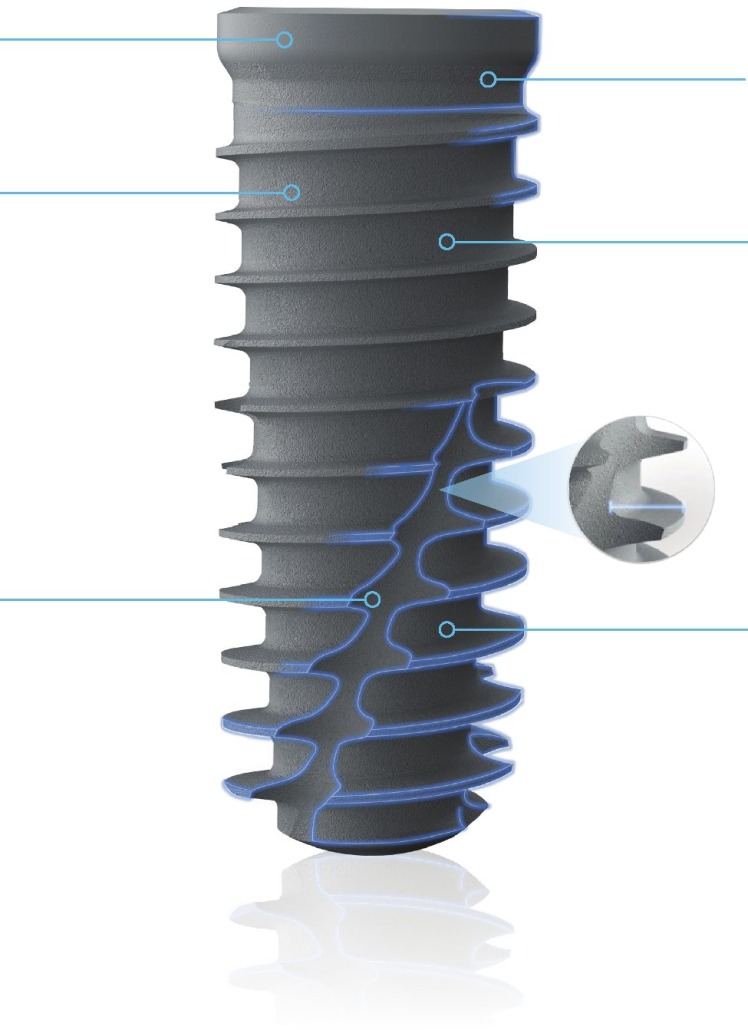

Estabilidad primaria

El contacto inicial entre el hueso y el implante es el principal responsable de la estabilidad del implante. Las especificaciones de los implantes T3® de ZimVie® están sujetos a rigurosas tolerancias para ofrecer un íntimo ajuste entre el implante y la osteotomia, creando un sistema de implantes dentales que ayuda a conseguir estabilidad primaria.

Osteointegración

En estudios preclínicos, los implantes T3® con superficie DCDR de ZimVie® han demostrado un aumento de la fuerza de integración durante la fase de cicatrización comparada con superficies con topografías menos complejas.

Mitigación del riesgo de Peri-implantitis

El implante T3® de ZimVie® utiliza la probada tecnología de superficie OSSEOTITE® en la zona coronal del implante. En el estudio realizado, con cinco años de seguimiento, la superficie con doble grabado ácido del implante OSSEOTITE® no presentó mayor riesgo de peri-implantitis ni de complicaciones del tejido blando, en comparación con superficies mecanizadas.*

*Estudio multicéntrico, aleatorizadamente controlado, de 5 años de duración sobre la incidencia de peri-implantitis en implantes híbridos e implantes con grabado ácido en toda la superficie del implante.

Topografía de superficie híbrida contemporánea (gruesa y fina)

Superficie micrométrica fina:

En el cuello la superficie del implante es Osseotite® (grabado ácido doble), lo que permite una protección contra la periimplantitis. Tiene rugosidades micrométricas finas que van de 1 a 3 micras.

Superficie micrométrica gruesa:

En el cuerpo del implante existe una transición hacia una superficie más rugosa que favorece la oseointegración. Las rugosidades micrométricas gruesas en esta sección son mayores a 10 micras.